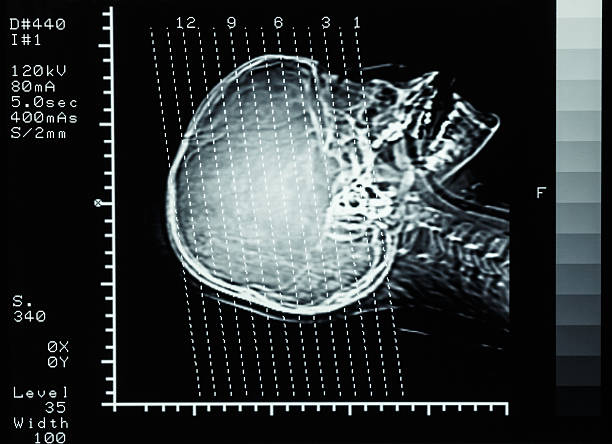

뇌경색 후유증은 심각한 장애를 남길 수 있는 신체적, 정신적 문제를 야기할 수 있는 중요한 주제입니다.

뇌경색 의심이 된다면 빠르게 대응해서 치료를 하는게 좋습니다.

뇌경색 후유증은 다양한 증상을 유발할 수 있습니다. 이러한 증상은 흔히 다음과 같이 나눌 수 있습니다.